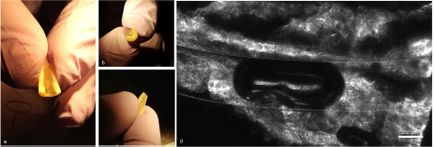

Representative images of pre-vascularized pulp-like tissue construct show cross-sectional views of a fabricated microchannel. (Image courtesy of Scientific Reports)

To address this issue, Bertassoni and colleagues used a 3D printing-inspired process -- based on their previous work fabricating artificial capillaries -- to create blood vessels in the lab. They placed a fiber mold made of sugar molecules across the root canal of extracted human teeth and injected a gel-like material, similar to proteins found in the body, filled with dental pulp cells. The researchers removed the fiber to make a long microchannel in the root canal and inserted endothelial cells isolated from the interior lining of blood vessels. After seven days, dentin-producing cells proliferated near the tooth walls and artificial blood vessels formed inside the tooth.